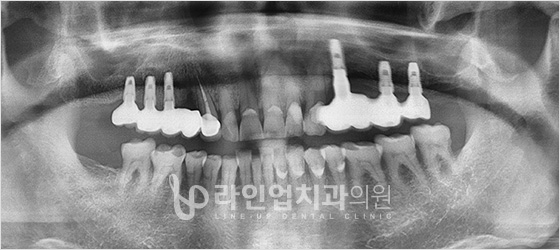

Before

After

Bottom molars implant